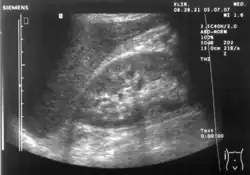

The hepatorenal recess[1] (subhepatic recess, pouch of Morison or Morison's pouch) is the subhepatic space that separates the liver from the right kidney. As a potential space, the recess is not normally filled with fluid. However, fluid can collect here in circumstances where the abdomen fills with fluid, such as hemoperitoneum. This fluid may be seen on ultrasound or computed tomography (CT scan).

Since it is a potential space, the hepatorenal recess is not normally filled with fluid. However, this space becomes significant in conditions in which fluid collects within the abdomen (most commonly ascites and hemoperitoneum). The intraperitoneal fluid, be it blood, ascites, or dialysate, collects in this space and may be visualized, most commonly via ultrasound or computed tomography (CT) scanning. As little as 30 or 40 ml of fluid in the abdominal cavity may be visualized in this space.

Early visualization of fluid in the hepatorenal recess on FAST scan may be an indication for urgent laparotomy.[2]